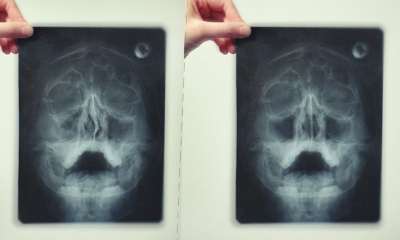

Как выглядит гайморит на рентгене

Определять гайморит на рентгеновском снимке (фото 5) учат еще в университетах. Здоровые носовые пазухи отображены темными полуовальными образованиями. Гайморит на снимке выглядит затемнением в верхних горизонтальных уровнях. По снимку можно четко проследить тень с волнистым контуром – жидкостью такого типа: гнойная, слизистая, катаральная.

Гайморит на рентгене

Почти всегда гайморит на рентгене (фото 6) выглядит как молоко в стакане: в черных пазухах имеется белое инфильтративное содержимое. Снимок пазух носа при гайморите вместе с диагностическими симптомами позволяет доктору вынести правильный диагноз. Однако когда скапливается гной при гайморите, патологические тени округлой формы не отслеживаются.